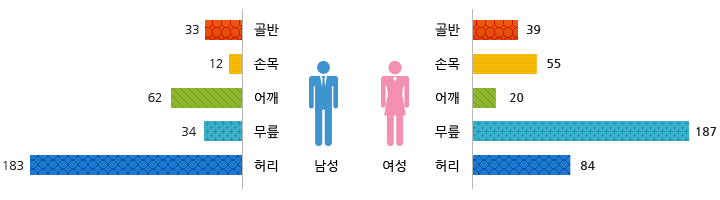

명절후유증으로 통증을 느끼는 부위는?

<2014년 2월, 9월 자생한방병원 내원 환자 370명 대상 조사 결과>